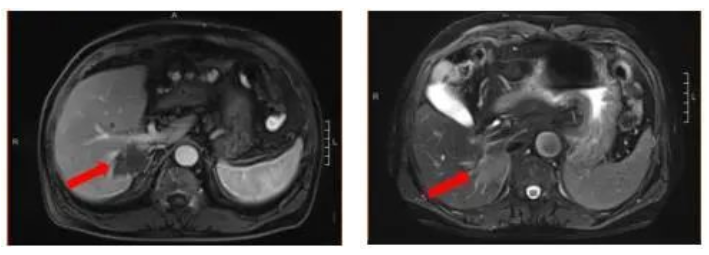

2021-12-21(治疗2周期后) 腹部增强MRI:胃壁增厚较前减轻,腹腔多发肿大淋巴结较前减小、较大者直径约1.6cm,肝脏病灶较前缩小、6.9*5.5cm,评效SD(缩小18%)

图3.治疗2周期后腹部增强MRI影像图

2022-02-04(治疗4周期后)胃壁增厚、腹腔多发肿大淋巴结无明显变化;肝脏病灶继续较前缩小、4.6*3.1cm,部分转移病灶消失,评效SD(缩小27%)

图4.治疗4周期后腹部增强MRI影像图